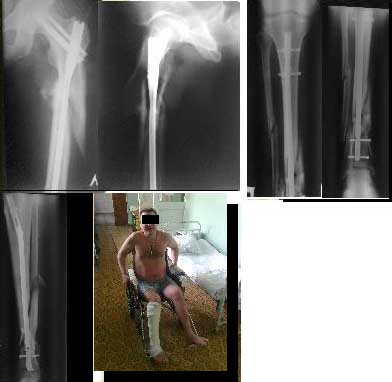

30/09/2011 синтез левого бедра PFN длинный на ортопедическом столе взакрытую.

5.10.2011 синтез правой голени стержнем Деост, в закрытую с применением дистрактора и остеотомией малоберцовой кости. Снимки в приложении. Пациент активизирован, начал передвигаться на коляске, сегодня встал с костылями.